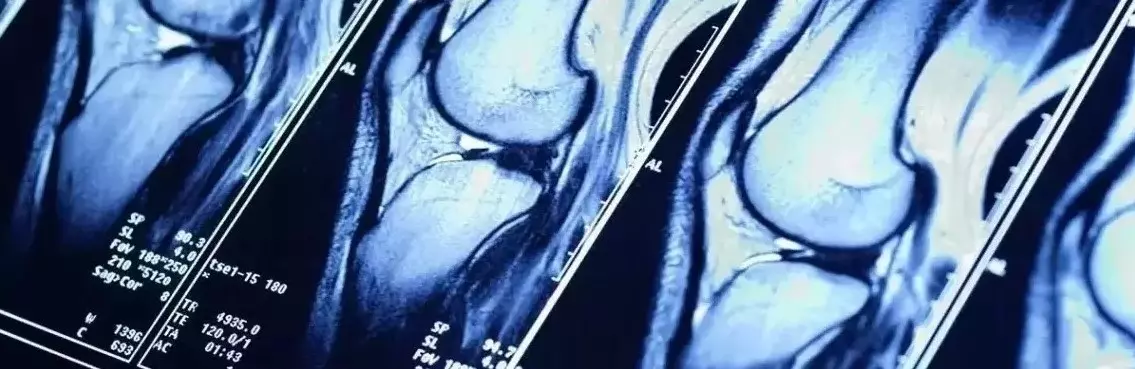

Choroba zwyrodnieniowa stawów, nazywana także chorobą degeneracyjną lub osteoartrozą, to najczęstsza choroba stawów, która prowadzi do niesprawności układu ruchu poprzez zaburzenie równowagi pomiędzy tworzeniem a degradacją chrząstki stawowej. W wyniku tego zaburzenia następuje rozmiękanie chrząstki, a z czasem dochodzi do jej ubytku, podczas gdy w zdrowym stawie mechanizmy odpowiadające za tworzenie i rozpad chrząstki pozostają w równowadze. Choroba zwyrodnieniowa stawów nierzadko bywa mylona z reumatoidalnym zapaleniem stawów – należy jednak podkreślić, że osteoartroza nie jest tym samym co reumatyzm. Co więcej, niektórym z nas może się mylnie wydawać, że choroba zwyrodnieniowa stawów występuje wyłącznie u ludzi starszych, którzy mają problemy z poruszaniem się ze względu na swój wiek. To nieprawda – choroba zwyrodnieniowa stawów może grozić nawet osobom aktywnym, w tym również zawodowym sportowcom. Dlaczego tak się dzieje? Jak to jest możliwe, że nawet osoby wysportowane są w grupie ryzyka choroby zwyrodnieniowej stawów? I jak odpowiednio zadbać o swoje stawy, będąc sportowcem?

Sportowcy, mimo że najczęściej nie zmagają się z nadwagą, również są narażeni na chorobę zwyrodnieniową stawów. Nasze stawy nierzadko ulegają nadmiernemu obciążeniu podczas uprawiania sportu. Za długie i zbyt intensywne treningi, brak odpowiedniej przerwy na regenerację (przetrenowanie organizmu), bagatelizowanie bólu pojawiającego się podczas ćwiczeń, uprawianie sportów wyczynowych (ekstremalnych) – to wszystko sprawia, że stawy sportowców są stale narażone nie tylko na chwilowe kontuzje, lecz także na negatywne efekty długofalowe, np. w postaci choroby zwyrodnieniowej stawów. Zmianom zwyrodnieniowym ulegają głównie stawy biodrowe, kręgosłup oraz stawy kolanowe, czyli wszystkie te, które przenoszą duże obciążenia. Należy jednocześnie podkreślić, iż wtórna postać osteoartrozy dotyka nawet osób przed trzydziestym rokiem życia. Choroba zwyrodnieniowa stawów może zatem stanowić poważne ryzyko dla aktywnie trenujących. Jak w takim razie zminimalizować ryzyko wystąpienia problemów ze stawami, kiedy jesteśmy osobami aktywnymi sportowo lub nawet zawodowymi sportowcami? Czy można odpowiednio zadbać o stawy podczas uprawiania sportu?